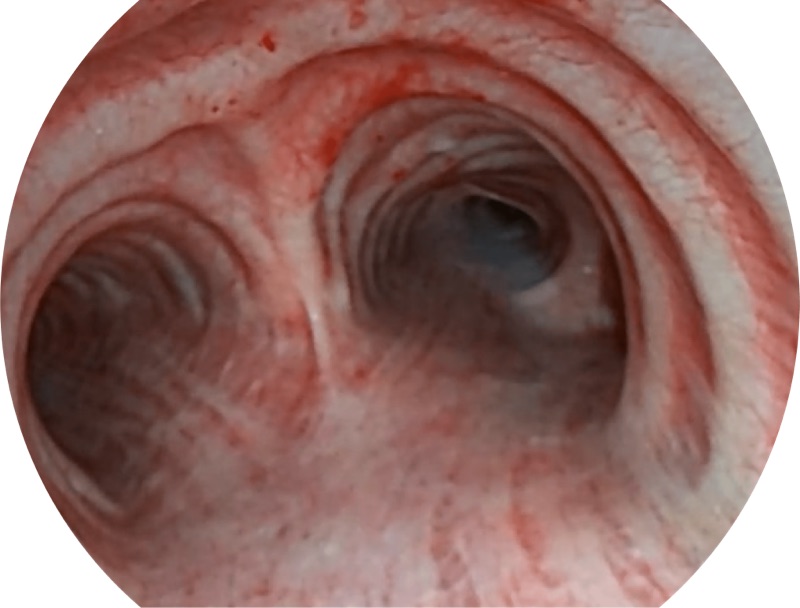

高清电子支气管内窥镜

帮助医生更加清晰地观察气管表面病灶

EB-5H20具有4.9mm外径及2.0mm钳道提升对外围支气管检查能力

白光

SFI

VIST